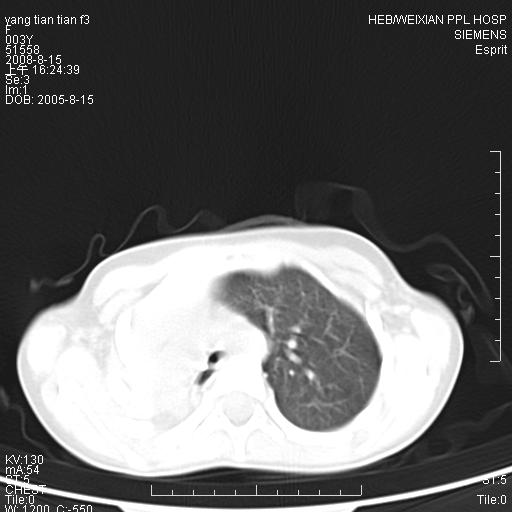

患儿,女,5岁,平素活动后气短,左侧面瘫.右侧胸廓较左侧塌陷.

两侧胸廓不甚对称,左侧稍膨隆,右肺体积明显变小,密度增高,未见正常通气肺组织,纵隔结构明显右移,心脏边缘欠清,外形似增大。纵隔血管间隙不清晰,左肺外形增大,部分肺组织突向右侧胸腔,左肺内未见异常密度影,右侧支气管逐渐变细,其内未见异常密度影。右侧未见叶及段支气管。右侧膈肌升高。

1。右肺体积小(考虑右肺发育不全)

2。左肺代偿性增大

3。心影增大?